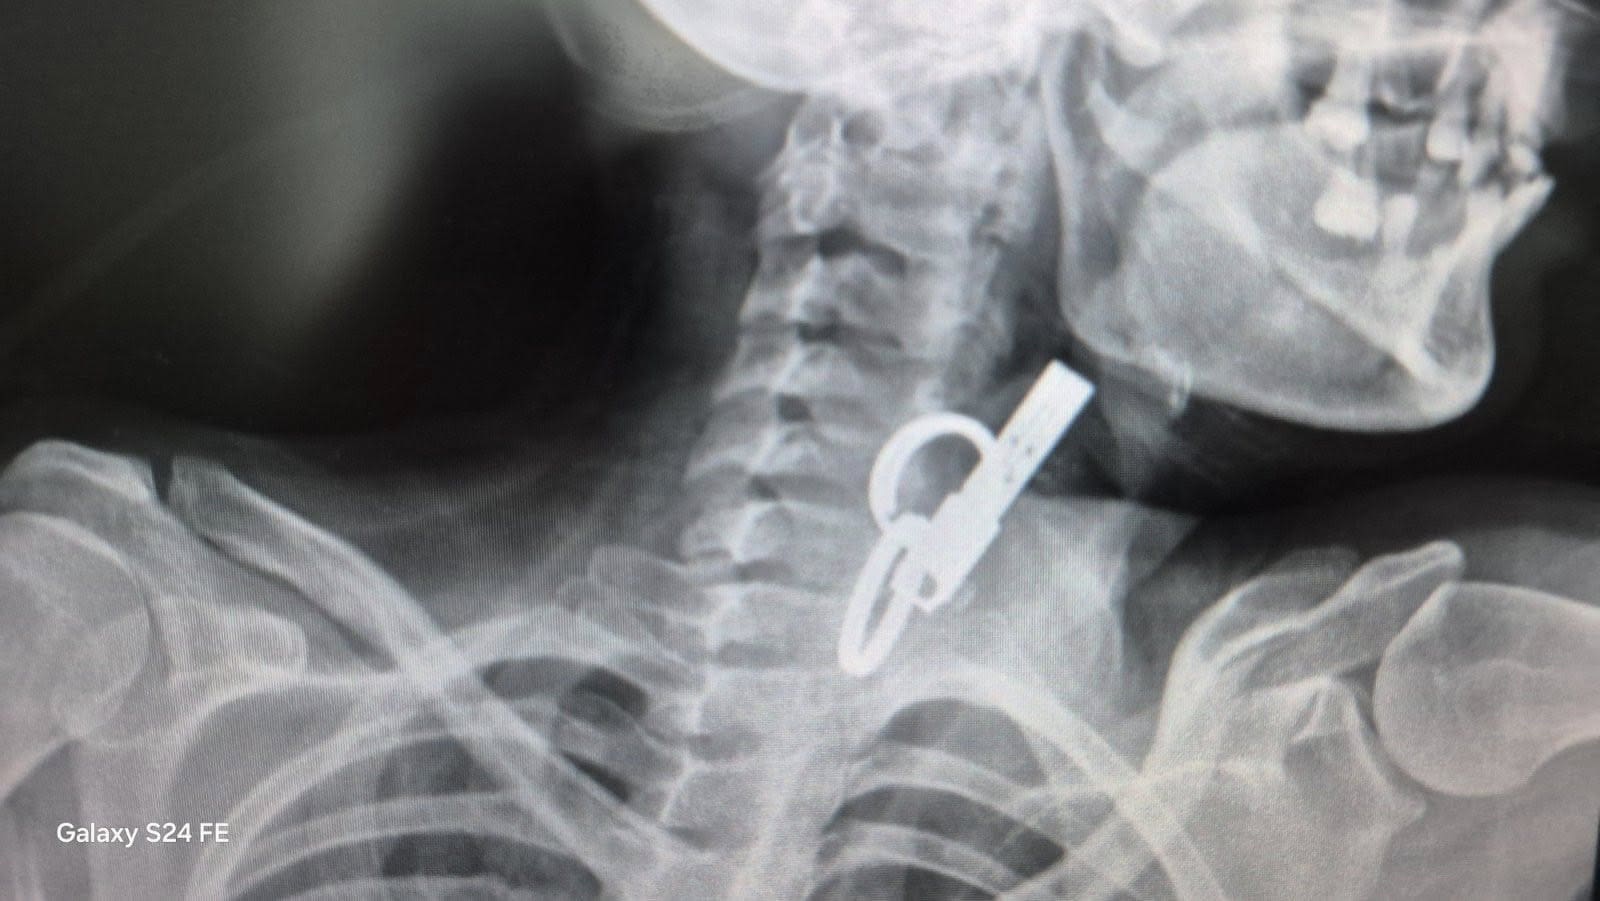

У Гусятині на Чортківщині лікарі успішно видалили зі стравоходу 40-річної жінки дверний ключ. Медичне втручання провели без хірургічного розрізу – за допомогою ендоскопічного обладнання. Про це повідомили у КНП «Гусятинська комунальна лікарня».

За інформацією медиків, пацієнтка проковтнула ключ навмисно – з особистих мотивів. До лікарні вона потрапила у шоковому стані. Після обстеження лікарі оперативно встановили причину та ухвалили рішення про невідкладне втручання.

Завдяки наявності сучасного ендоскопічного обладнання стороннє тіло вдалося видалити без відкритої операції.